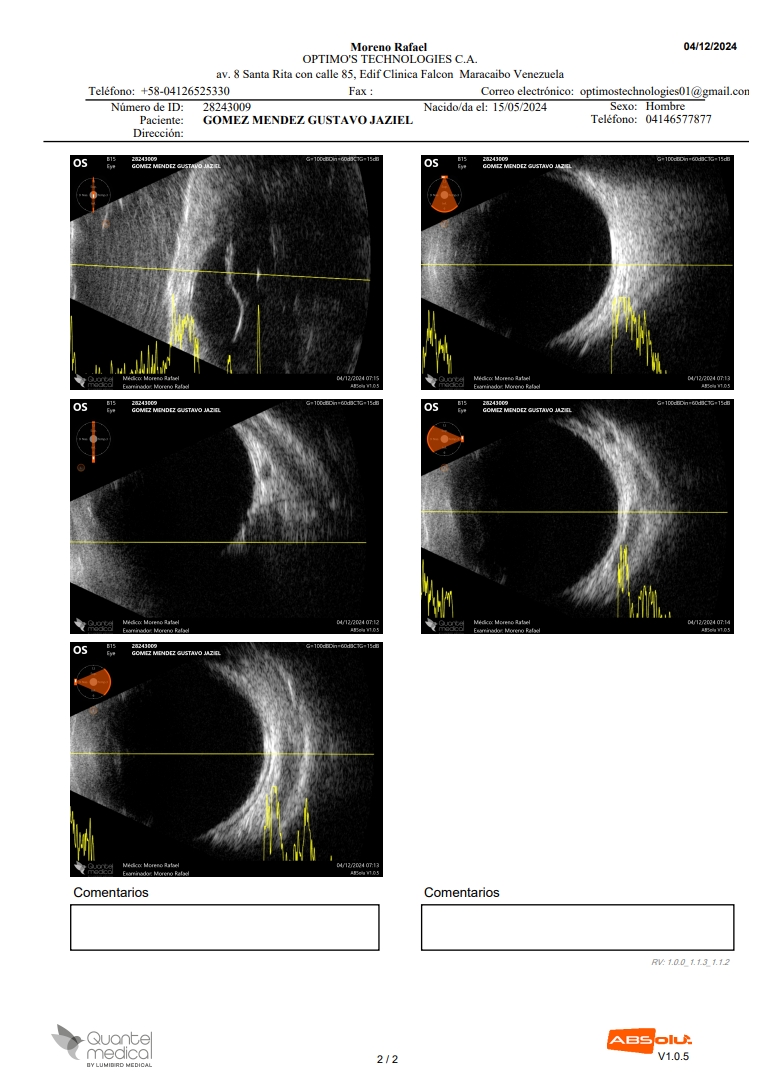

Gustavo Jaziel Gómez Méndez, de un año de edad, fue diagnosticado con glaucoma a los tres meses de nacido y estudios recientes revelaron que tiene una malformación en el ojo izquierdo llamado Síndrome Iridocorneal Endotelial (ICE, por su siglas en inglés), además de una catarata congénita.

El niño zuliano presentó una opacidad en sus ojos a los 90 días de nacido. Después de tratarlo diferentes médicos, en el Hospital Universitario de Maracaibo le diagnosticaron glaucoma y en exámenes posteriores se le detectó el ICE y catarata congénita.

Le notaron a Gustavo Jaziel “una forma de pico en el ojo”. Los médicos tratantes le afirmaron a su mamá que tiene “la córnea perforada y el ojo abierto”, dejándolo expuesto a contraer cualquier enfermedad bacteriana o contaminarse y que la única forma para tratarlo es efectuar la operación para cerrarlo.